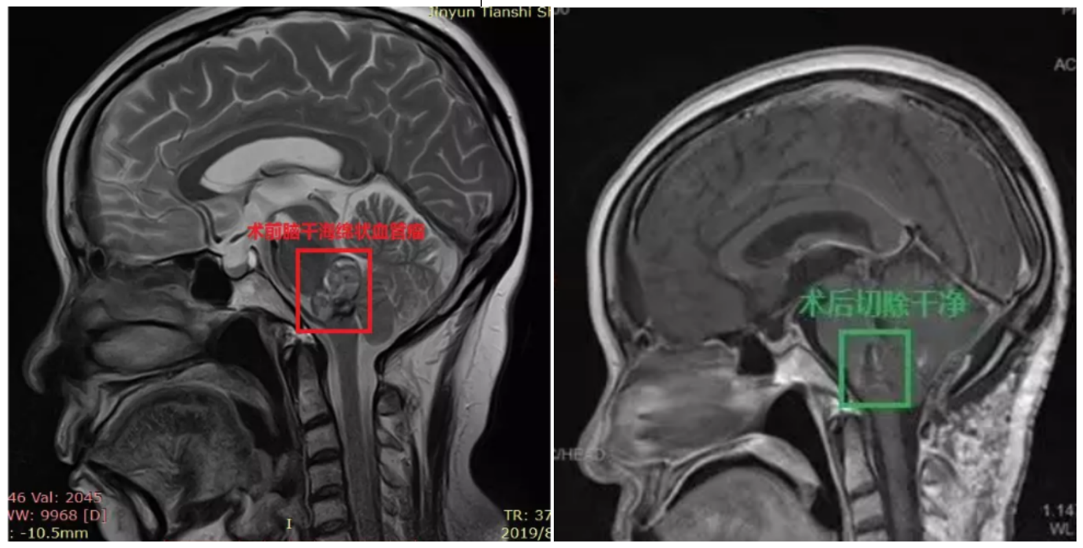

腦干海綿狀血管瘤出血案例術(shù)前診斷:腦干腦橋海綿狀血管瘤,出血活動期,壓迫四腦室

手術(shù)結(jié)果:顯微鏡下全切腫瘤,腫瘤切除歷時約1.5小時,手術(shù)順利。

術(shù)后48小時內(nèi)MR復(fù)查顯示腫瘤全切

功能狀態(tài)情況:術(shù)后一周,患者能獨自下床、少量活動,面部麻木消失,一側(cè)頭部麻木感較手術(shù)前好轉(zhuǎn),發(fā)音較術(shù)前好轉(zhuǎn),無其他手術(shù)相關(guān)并發(fā)癥,術(shù)后10天左右順利拆線,術(shù)后2周出院。